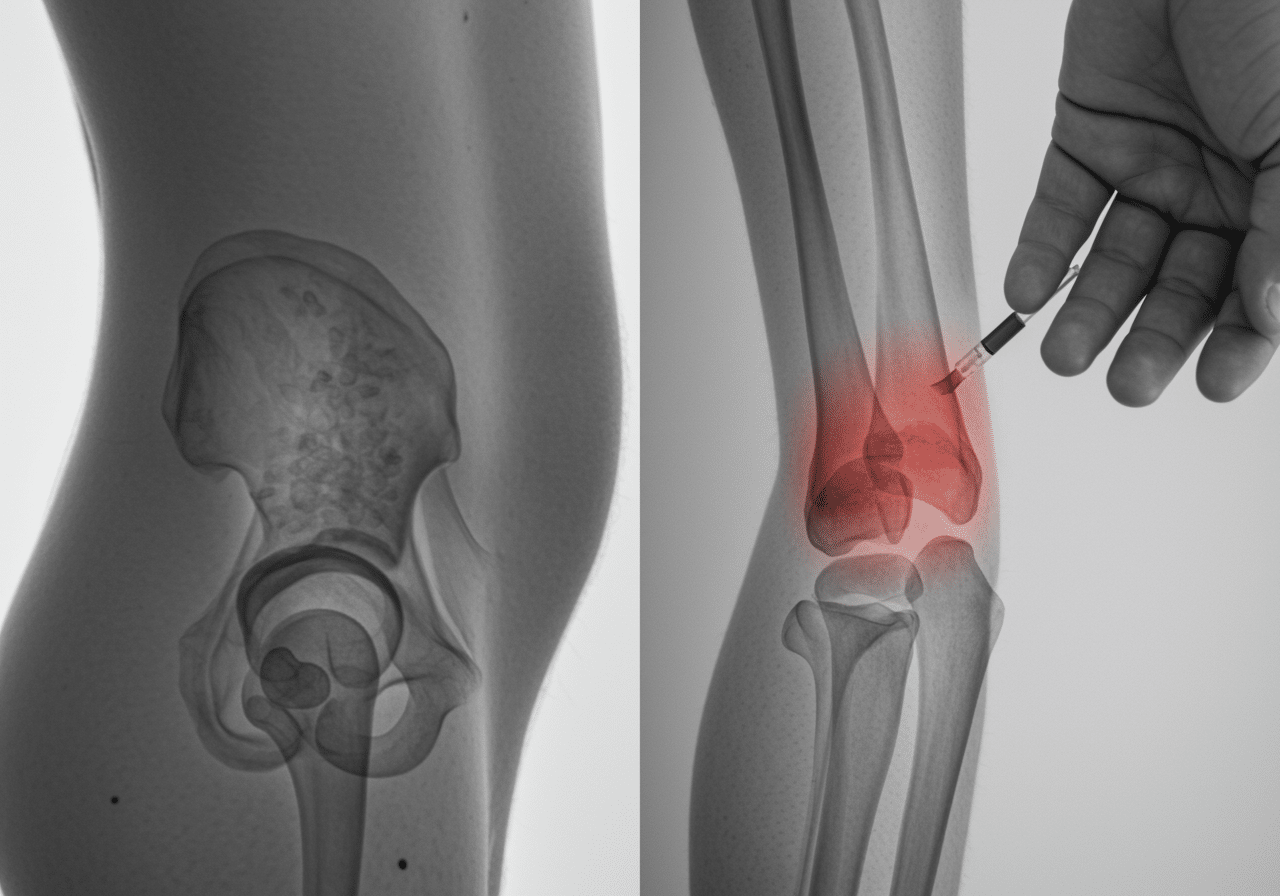

Advanced Orthopedic Treatment Technology: Beyond Basic Fracture Care

Priority ER's diagnostic capabilities for open (compound) and closed long-bone fractures exceed Joint Commission standards for emergency departments[14], featuring advanced digital radiography systems providing immediate fracture visualization with 30% better resolution than standard urgent care facilities. Our multiple-view x-ray protocols identify fracture displacement, comminution patterns, and joint involvement requiring surgical fixation, while our emergency physicians trained in Gustilo-Anderson classification assess open fracture severity guiding antibiotic selection and debridement urgency[15]. The integration of procedural sedation capabilities allows pain-free fracture reduction that urgent care facilities cannot provide without hospital transfer.

Advanced imaging through our comprehensive diagnostic capabilities provides CT scanning for complex fractures, assessing intra-articular extension and fracture fragment displacement requiring operative fixation that plain x-rays cannot fully visualize. For pediatric cases, our emergency physicians employ specialized growth plate assessment preventing physeal bar formation and limb length discrepancies that improper treatment causes. This comprehensive approach explains why the American Academy of Orthopaedic Surgeons recommends emergency departments over urgent care for all suspected long-bone fractures requiring reduction, open fracture management, or neurovascular monitoring unavailable in limited-capability urgent care settings.

Fracture Treatment Process at Priority ER: Zero Wait Orthopedic Care

Upon arrival at Priority ER for open (compound) and closed long-bone fractures, patients bypass traditional triage delays through our trauma protocol. Board-certified emergency physicians trained in orthopedic emergency care begin assessment immediately, with digital x-rays performed within 10 minutes and fracture stabilization initiated within 30 minutes of arrival[9]. This comprehensive approach identifies complex fracture patterns that urgent care facilities would miss entirely, such as intra-articular involvement requiring surgical fixation or neurovascular compromise necessitating immediate reduction and vascular surgery consultation.